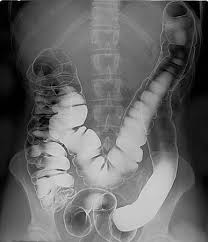

اگر بخواهیم کاربرد دقیقترش را توضیح دهیم: زمانی که بیمار مقدار مناسبی از سوسپانسیون باریم سولفات را نوشیده یا در روده بزرگ با تنقیه وارد شده باشد، دیوارههای داخلی مری، معده، رودهها یا روده بزرگ با این ماده پوشیده میشود و در تصویر پرتوی X یا سیتیاسکن، بخشهایی که اندام ها میپوشانند و یا بخشهایی که راه عبور دارند، به رنگ سفید یا بسیار روشن دیده میشوند؛ بنابراین ساختار، اندازۀ لومن (فضای داخلی)، وجود هرگونه تنگی، زخم، تومور یا التهاب را رادیولوژیست بهتر تشخیص میدهد. مثلاً در روش معروف بالع باریم (barium swallow) یا تنقیه باریم (barium enema) این فناوری به کار میرود.

ابتدا پودر باریمسولفات (یا مایع آماده) تهیه میشود. این پودر با آب یا محلول مخصوص مخلوط میگردد تا سوسپانسیونی یکنواخت حاصل شود. افزودنیهایی همچون عامل غلظتدهنده، طعمدهنده یا امولسیفایر ممکن است در این بین اضافه شوند تا بلع بیمار آسانتر شود و رسوب ذرات کاهش یابد. سپس بیمار یا به صورت خوراکی (برای بررسی مری، معده، روده کوچک) یا به صورت تنقیه (برای روده بزرگ) از این سوسپانسیون استفاده میکند. برای مثال در بررسی روده بزرگ via تنقیه باریم، معمولاً ابتدا روده پاکسازی میشود (ناشتا بودن، رژیم مایع، یا داروی ملین) تا مواد باقیمانده در روده تصویر را مخدوش نکنند. سپس میزان مناسب باریم داخل روده قرار میگیرد و تصویربرداری با فلوروسکوپی یا X-ray صورت میگیرد. در برخی مراحل کنتراست دوگانه (double contrast) نیز انجام میشود، یعنی نه تنها باریم وارد میشود، بلکه هوا یا گاز نیز به داخل روده وارد میگردد تا دیواره روده بهتر از پسزمینه مشخص شود.